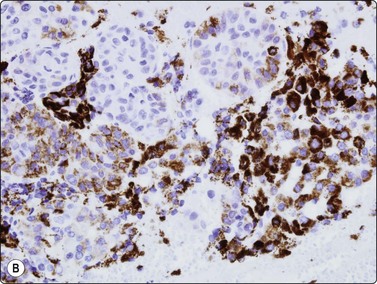

image

Fig. 10.25 Hepatocellular carcinoma

CD34 immunostaining demonstrates the classic endothelial staining pattern which is absent in reactive liver cell block (CD34, HP).

image image

Fig. 10.26 Hepatocellular carcinoma

(A) pCEA immunostaining shows cytoplasmic staining along canalicular luminal edges only (pCEA, HP); (B) HepPar-1 produces diffuse granular cytoplasmic staining in distinction to adenocarcinoma, which is negative (HepPar-1, HP).

image image image

CD34 and factor VIII immunostaining have been used in demonstrating the classic endothelial staining pattern of HCC (Fig. 10.25), absent in reactive liver and metastatic carcinoma,139 but are limited by partial staining of adenoma and focal nodular hyperplasia. Indeed, they provide little more information than the less expensive reticulin.131,139-141 Over-expression of Glypican-3, a heparan sulphate proteoglycan that plays an important role in cell growth and differentiation, has been observed in malignant hepatocytes. In several studies on cytological smears, positive staining for Glypican-3 showed a high sensitivity (80–90%) and specificity (> 95%) in HCC versus metastatic tumors and benign liver lesions.142-144

Various antibodies have been used to differentiate between hepatocellular carcinoma, cholangiocarcinoma and metastatic malignancies of various types.151,152 Positive immunoperoxidase staining for alpha fetoprotein favors primary cancer, but is seen in only around 50% of HCCs.129,153,154 It has good specificity despite also staining some germ cell tumors and occasional hepatoid adenocarcinomas of the gastrointestinal tract.

The demonstration of a characteristic bile canalicular staining pattern in HCC by means of polyclonal carcinoembryonic antigen (pCEA) is useful although it decreases with increasing anaplasia. Whereas metastatic adenocarcinoma displays full cytoplasmic immunostaining, HCC will show staining only along canalicular luminal membrane (Fig. 10.26A).73,116,129,154-158 Reported sensitivity ranges from 47% to 90%. It is essential that the polyclonal antibody be used; the same results will not be observed with the monoclonal antibody. Staining for CD10 gives the same pattern as CEA but is negative in adenocarcinoma.159,160

HepPar-1 is an antibody which recognises mitochondria in both benign and malignant hepatocytes. It has recently proved highly sensitive and specific in the distinction between adenocarcinoma and HCC, producing diffuse granular cytoplasmic staining in the latter (Fig. 10.26B).156,161,162